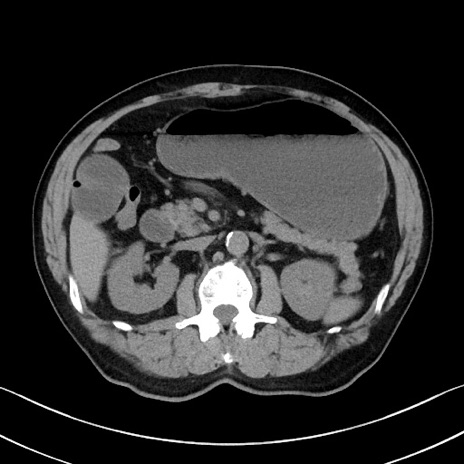

症例35(横断像)

【症例】70歳代 男性

【主訴】腹部膨満、嘔吐

【現病歴】昨日より腹部膨満感出現。本日増悪し、仙痛出現。嘔吐あり、受診。

【既往歴】糖尿病、胆摘後

【身体所見】BP 149/80mmHg、HR 74/min、BT 35.9℃、腹部:膨満、軟、圧痛なし。腸雑音減弱あり。上腹部正中切開瘢痕あり。

【データ】WBC 13500、CRP 1.72